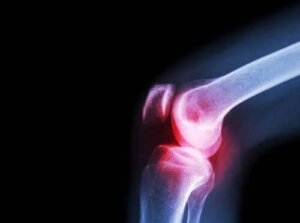

Este important să subliniem faptul că majoritatea cazurilor de artrită septică sunt cauzate de bacterii, în special de stafilococi și streptococi. Deși poate apărea la orice vârstă, artrita septică apare cel mai frecvent la sugari. Mai mult, afectează în principal șoldul sau genunchiul.

Simptomele artritei septice variază în funcție de tipul de infecție. Infecțiile bacteriene tind să afecteze doar o articulație – de obicei, genunchiul sau șoldul. În acest caz, orice mișcare a articulației afectate este foarte dureroasă. Această durere, precum și alte simptome, inclusiv febra și frisoanele, tind să se dezvolte rapid.

Apoi, medicii pot efectua și o radiografie a articulației afectate. Razele X și alte instrumente de diagnosticare pot ajuta la evaluarea daunelor.